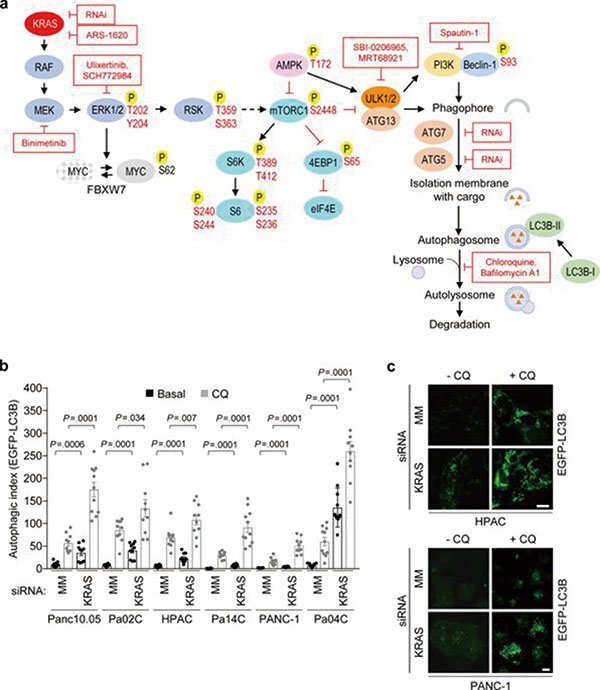

同期,北卡罗莱纳大学Bryant等也发现,抑制RAS可直接通过信号传导机制,以及间接通过对细胞代谢的影响,促进癌细胞的自噬,并增强癌细胞对自噬的依赖性。联合使用自噬抑制剂和RAS下游的ERK抑制剂,可有效抑制RAS驱动的胰腺癌细胞。

研究者发现,使用MEK抑制剂曲美替尼,或抑制ERK,抑或直接抑制RAS,都能让胰腺癌细胞中的自噬进一步增加。考虑到自噬对于细胞稳态的维持作用,或许这就是靶向RAS信号通路的疗效不佳的原因。

既然癌细胞可能靠自噬来抵御靶向治疗,那再把自噬抑制住不就行了吗?研究者将曲美替尼和自噬抑制剂氯喹联合使用,发现确实明显抑制了癌细胞的生长。向癌细胞中转入自噬抑制基因,也同样让它变得对曲美替尼敏感。提示正是自噬在靶向治疗中保护了癌细胞。

北卡罗莱纳大学的研究中,研究者进一步分析了抑制RAS通路如何增加癌细胞自噬。研究发现,抑制RAS下游的ERK,引起AMPK信号的激活和mTORC1信号的抑制。而这两种信号变化,都会导致自噬的增加。抑制ERK还会抑制细胞的糖酵解,从而让癌细胞更依赖自噬供能。此外,ERK的抑制还可能通过影响核苷酸的代谢促进自噬。